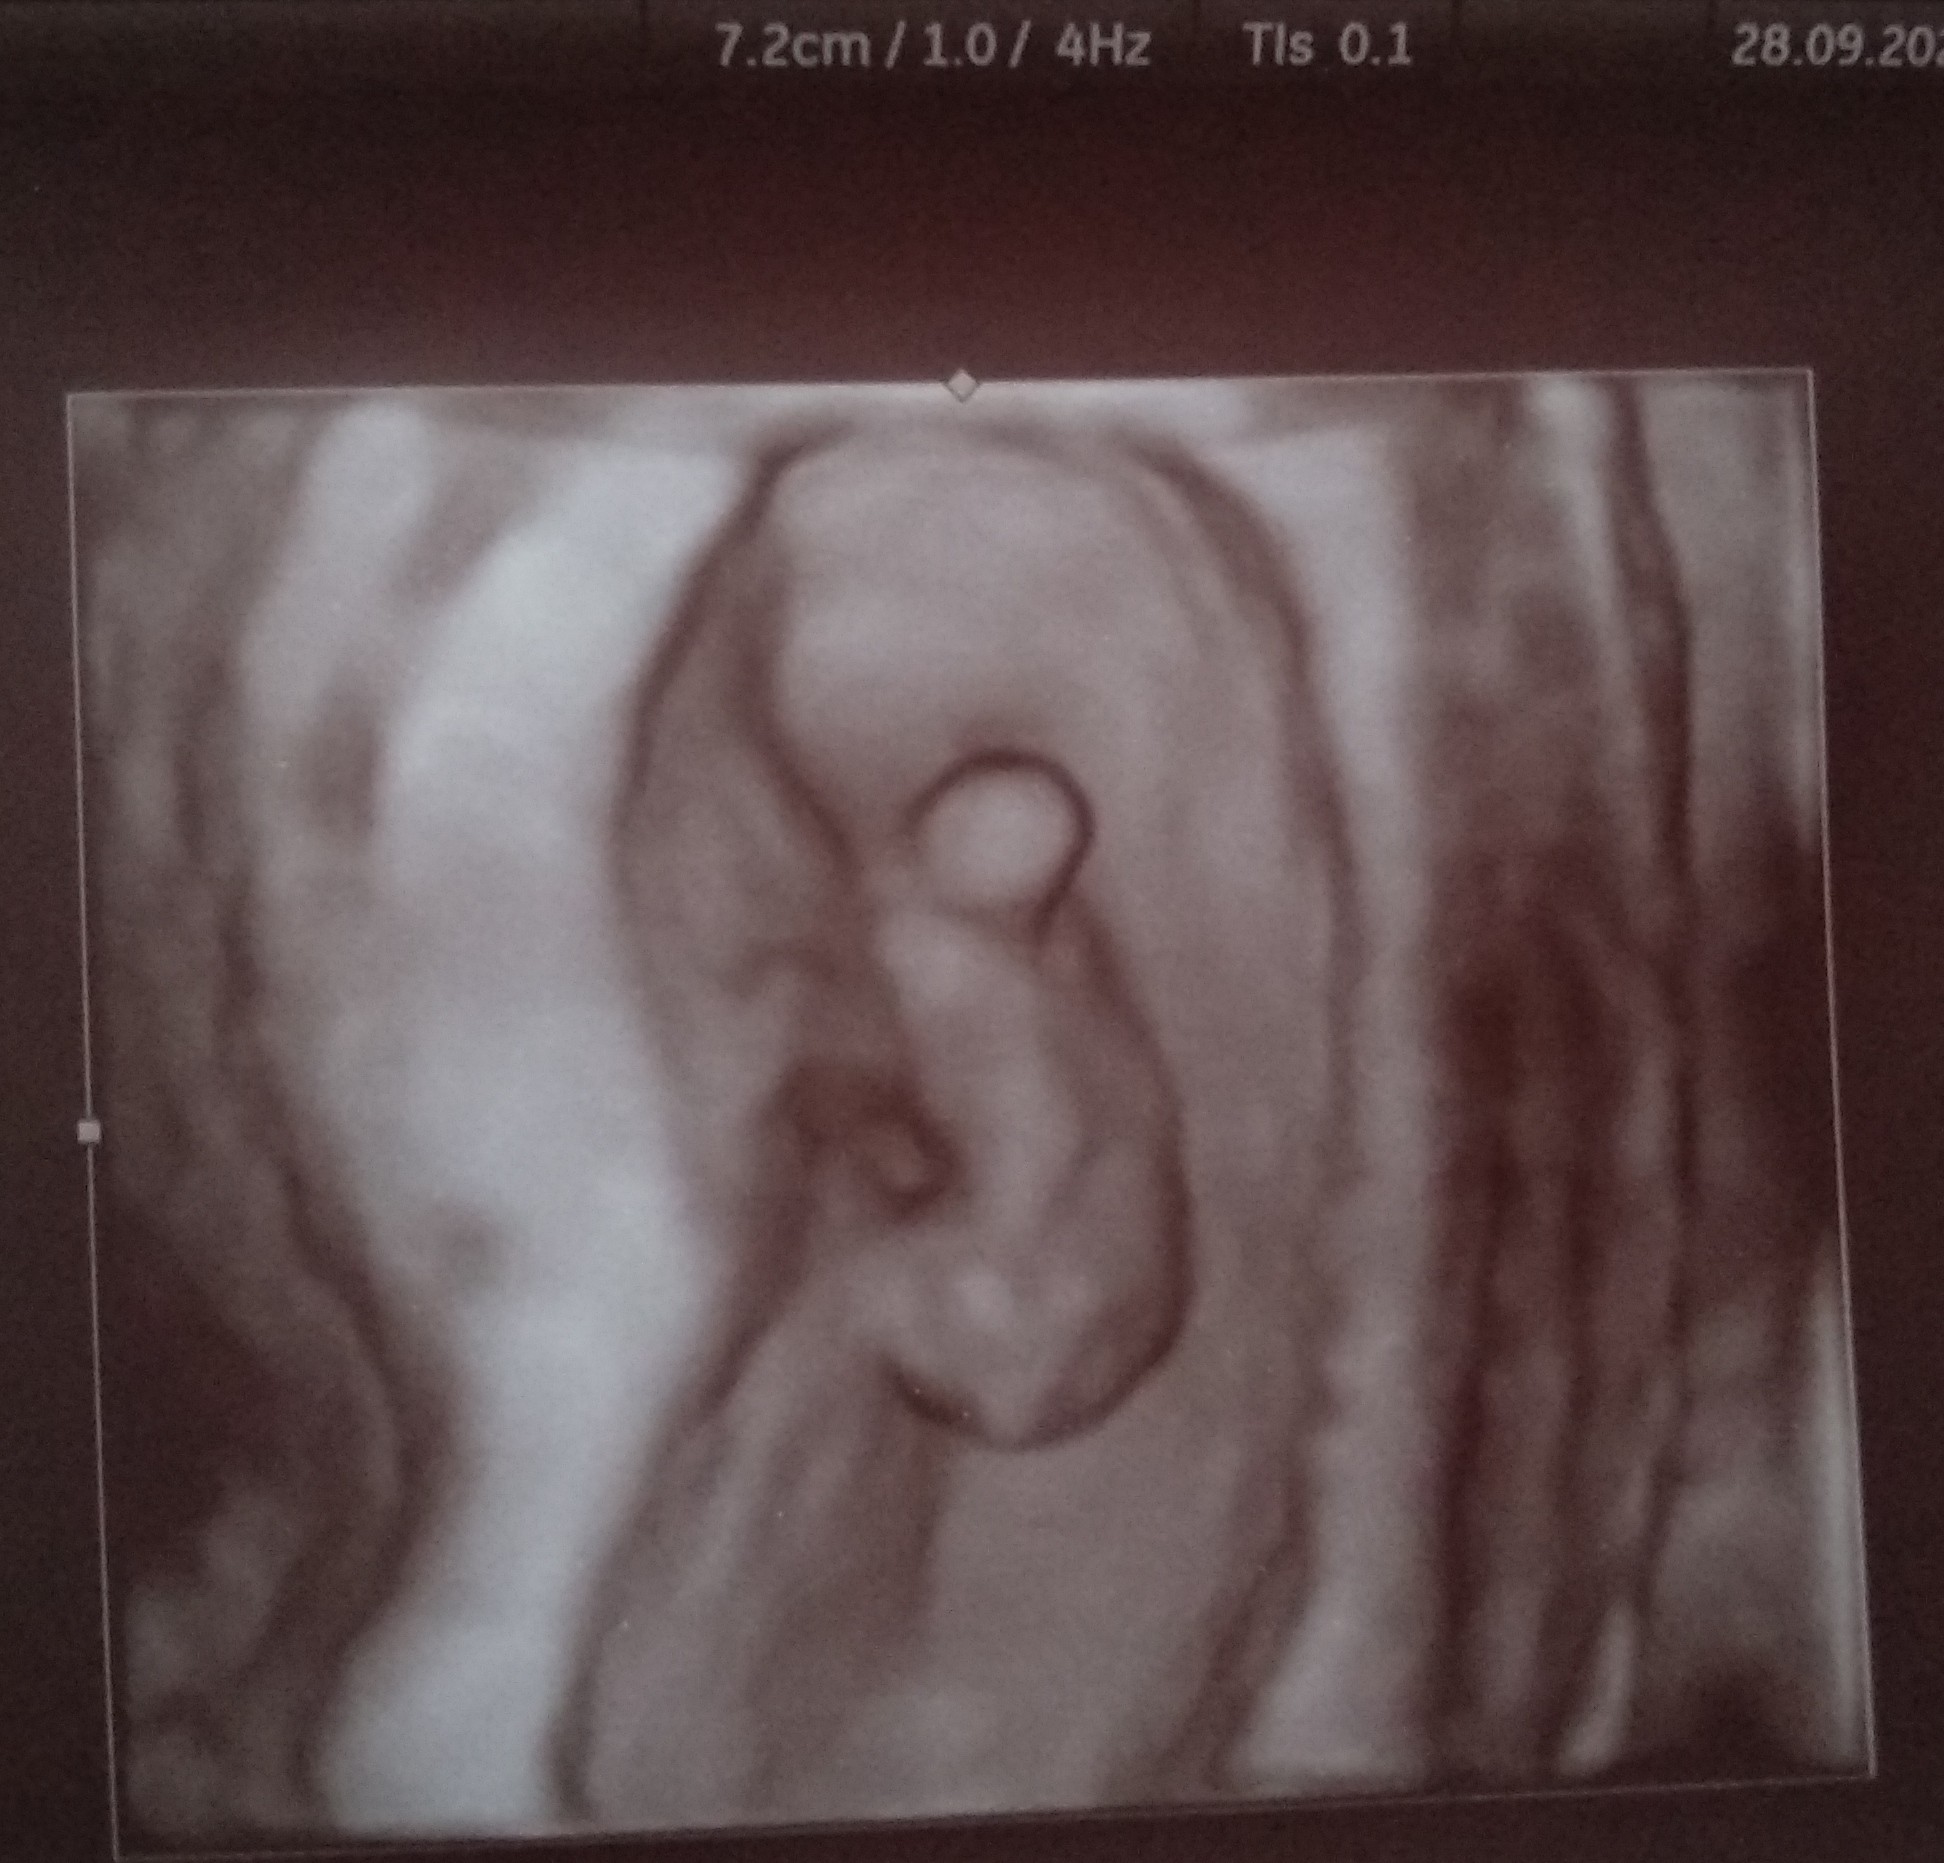

A tutaj focia mojego bąbla 😍

Jestem po wizycie ♥

Jest dobrze - serduszko ładnie sobie bije, zarodek jest ☺

Wg @ 8+2, a wg USG powiedział, że 8+6.

USG już przez brzuszek 😊

Mam dalej brać duphaston i luteinę.

Kolejna wizyta za 3 tygodnie - 19.10 ☺️